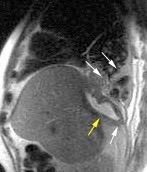

Hallazgos en RM .

Buena en casos dudosos

Cortes sagitales y coronales: Interrupción de la línea diafragmática

Paciente que ingresa con síntomas de colecistitis aguda. Antecedentes de trauma importante muchos años antes

Zhao L et al. Delayed traumatic diaphragmatic rupture: diagnosis and surgical treatment. © Journal of Thoracic Disease.

J Thorac Dis 2021

Asas

Líquido pericolecistítico

V. biliar con cálculos

Diafragma